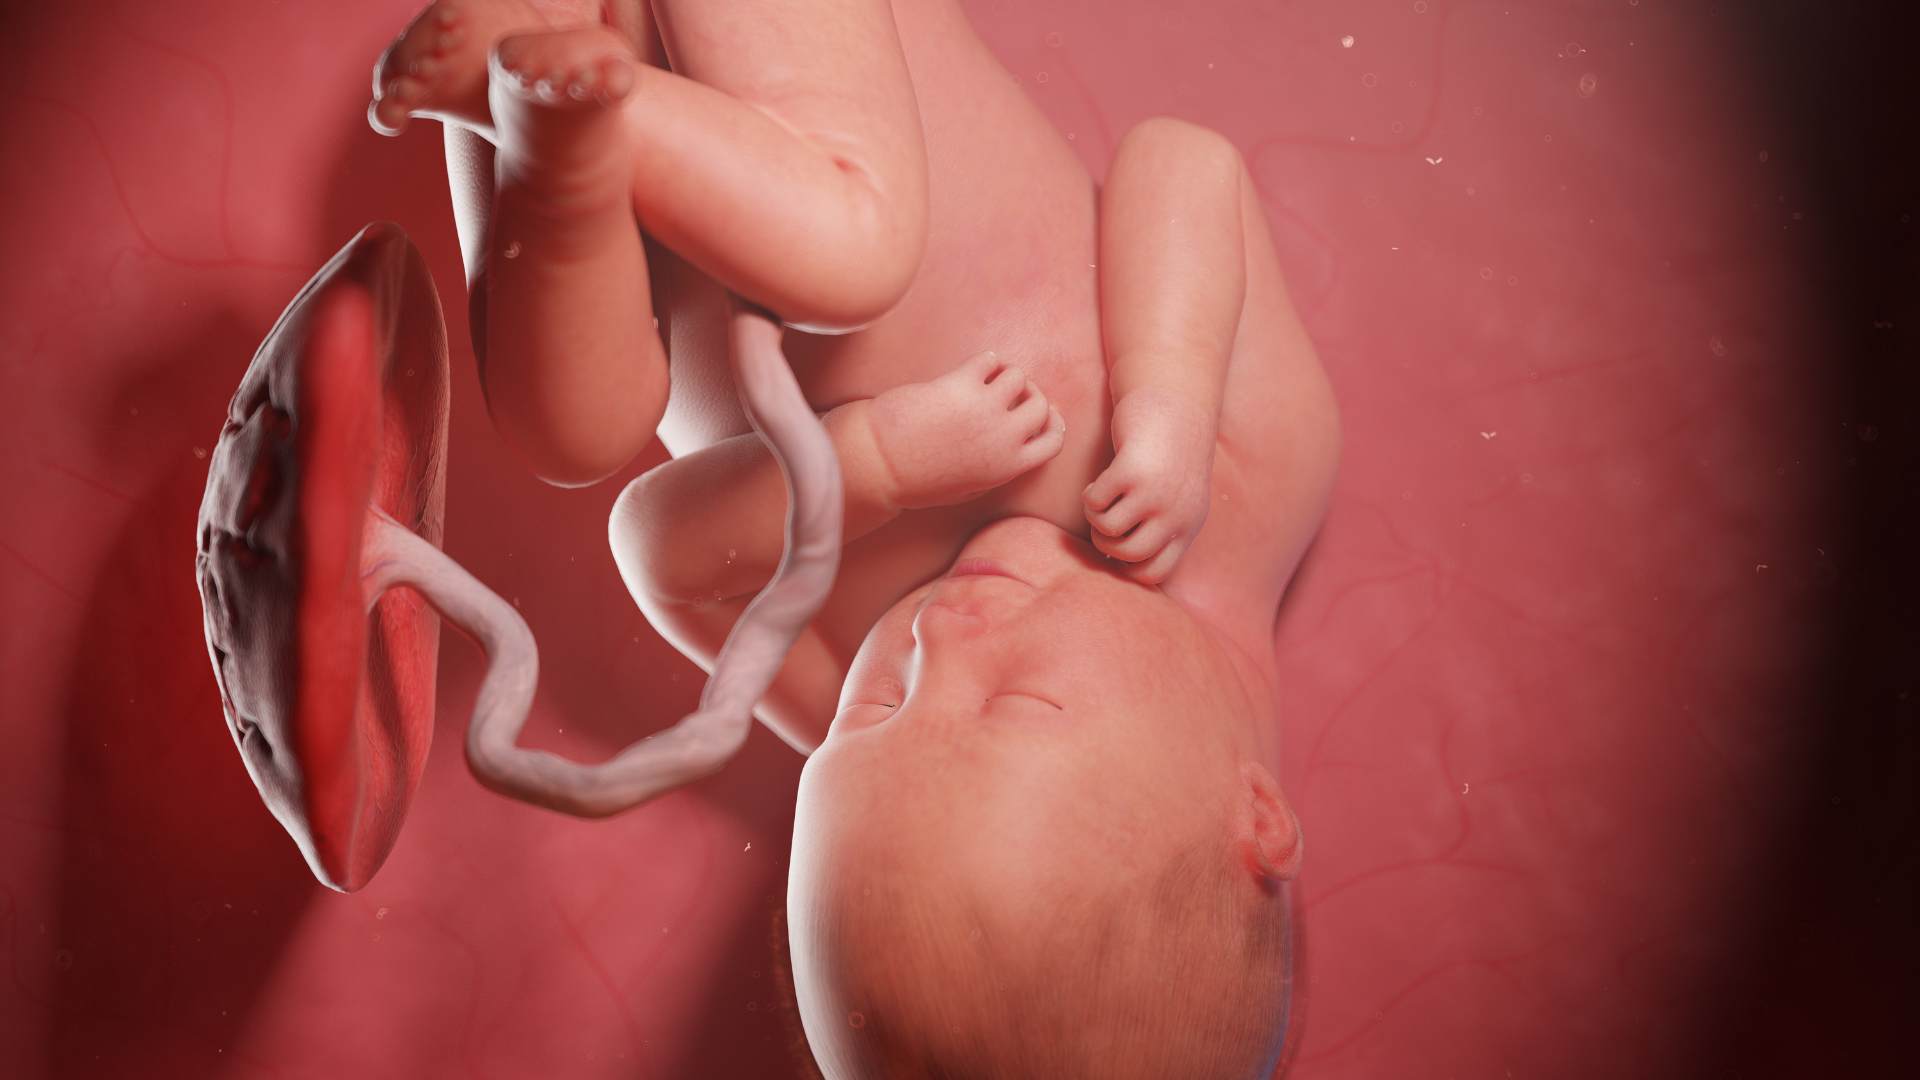

Nước ối đảm nhận nhiều chức năng sinh học quan trọng giúp thai nhi phát triển khỏe mạnh và tạo điều kiện thuận lợi cho mẹ trong quá trình mang thai.

Bảo vệ thai nhi khỏi va chạm và nhiễm trùng

Túi ối chứa nước ối hoạt động như một lớp đệm tự nhiên, giúp giảm thiểu tác động từ các chấn động bên ngoài như mẹ đi lại, xoay người, vận động hoặc những va chạm nhẹ vào vùng bụng. Lớp dịch này cũng ngăn ngừa sự xâm nhập của vi khuẩn từ âm đạo vào buồng tử cung, giảm nguy cơ nhiễm trùng ối - một tình trạng nguy hiểm có thể gây sinh non hoặc đe dọa tính mạng thai nhi.

Giúp thai nhi vận động, phát triển cơ - xương

Không gian chứa nước ối giúp bé dễ dàng thực hiện các chuyển động như xoay người, duỗi tay chân, đá chân hoặc nắm bàn tay. Những vận động này kích thích sự phát triển của hệ cơ - xương, giúp thai nhi hoàn thiện cấu trúc xương khớp. Nếu không đủ nước ối, thai nhi dễ bị hạn chế vận động, dẫn đến biến dạng chi hoặc nguy cơ chèn ép dây rốn.

Duy trì nhiệt độ ổn định trong tử cung

Môi trường nước ối luôn giữ nhiệt độ ổn định, giúp thai nhi không bị ảnh hưởng bởi sự thay đổi nhiệt độ cơ thể mẹ hoặc môi trường bên ngoài. Nhờ đó, bé được phát triển trong điều kiện ổn định nhất.

Hỗ trợ trao đổi chất và cung cấp dinh dưỡng

Trong giai đoạn đầu thai kỳ, nước ối chứa glucose, điện giải và các chất dinh dưỡng mà thai có thể hấp thu qua da. Nước ối đồng thời tham gia vào quá trình trao đổi chất giữa mẹ và thai, giúp đào thải chất thải của thai qua nhau thai. Sự trao đổi liên tục này duy trì môi trường sạch và giàu dinh dưỡng cho bé.